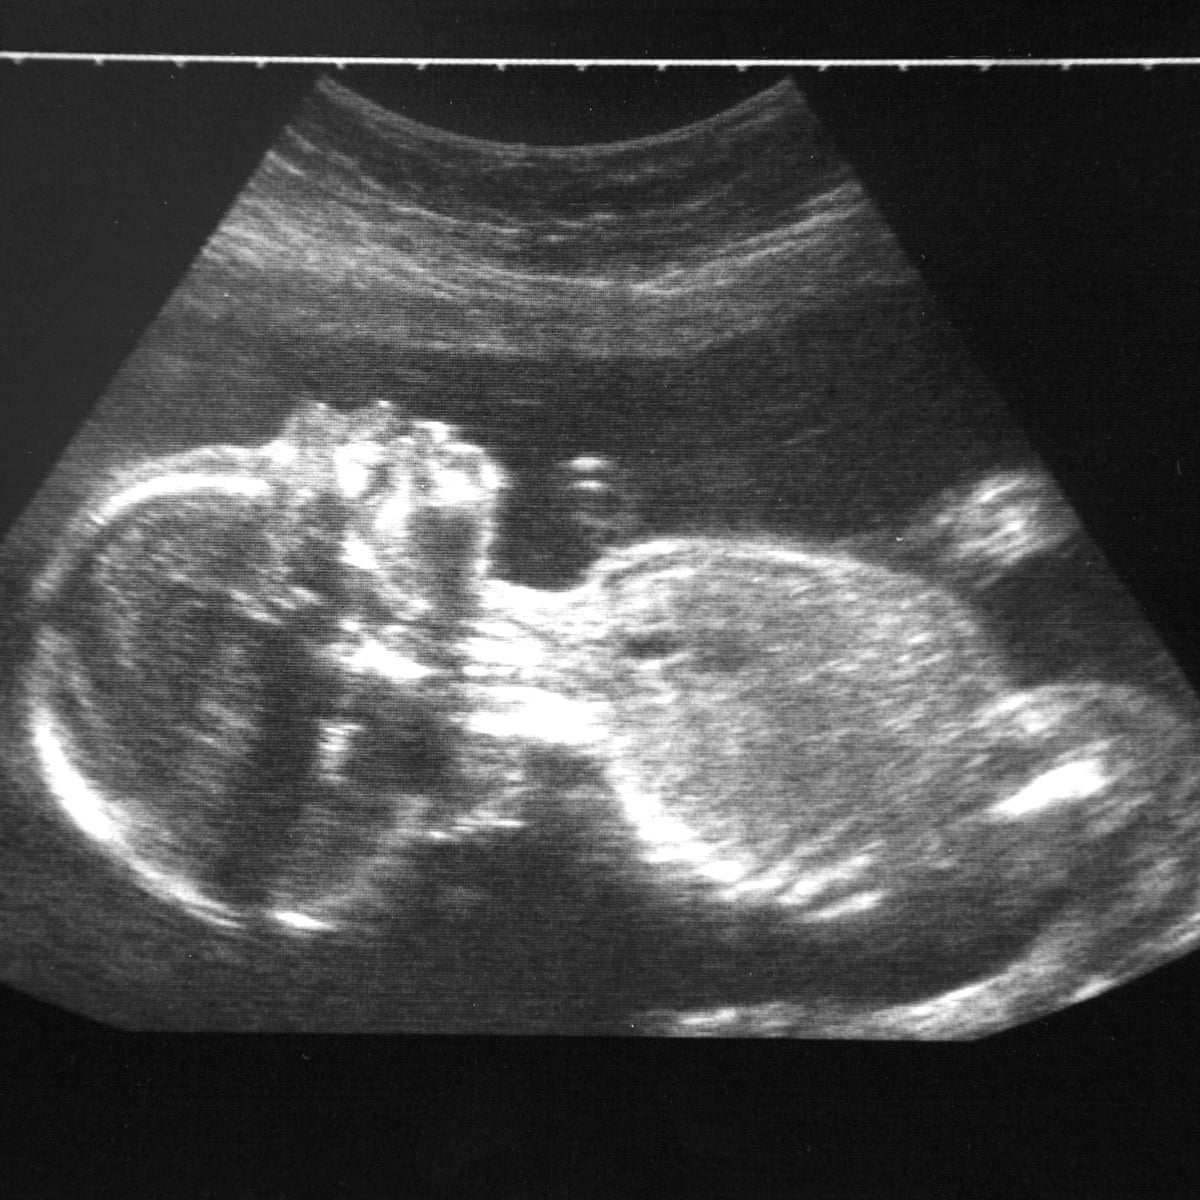

বেলজিয়ামের হ্যাসেল্ট বিশ্ববিদ্যালয়ের অধ্যাপক টিম নওরোট ও তাঁর টিম এই গবেষণা চালিয়েছেন। সেই গবেষণাপত্রে দাবি করা হয়েছে, শহরাঞ্চলগুলির দূষিত এলাকায় গর্ভস্থ শিশুর মস্তিষ্ক, ফুসফুস এবং যকৃতে দূষিত কণা (Air Pollution) পাওয়া গেছে। প্রসূতিদের ওপর গবেষণা চালিয়ে বিজ্ঞানীরা দেখেছেন, বাতাসের দূষিত কণা, ধোঁয়া, কার্বন-ডাই-অক্সাইড মায়ের থেকে শিশুর শরীরেও ঢুকছে। ফলে প্রসবের আগেই গর্ভস্থ শিশুর মস্তিষ্ক, ফুসফুসে সেই বিষাক্ত কণা (Air Pollution) ঢুকে যাচ্ছে যা পরবর্তী সময়ে দুরারোগ্য জটিল রোগের কারণ হয়ে উঠতে পারে।